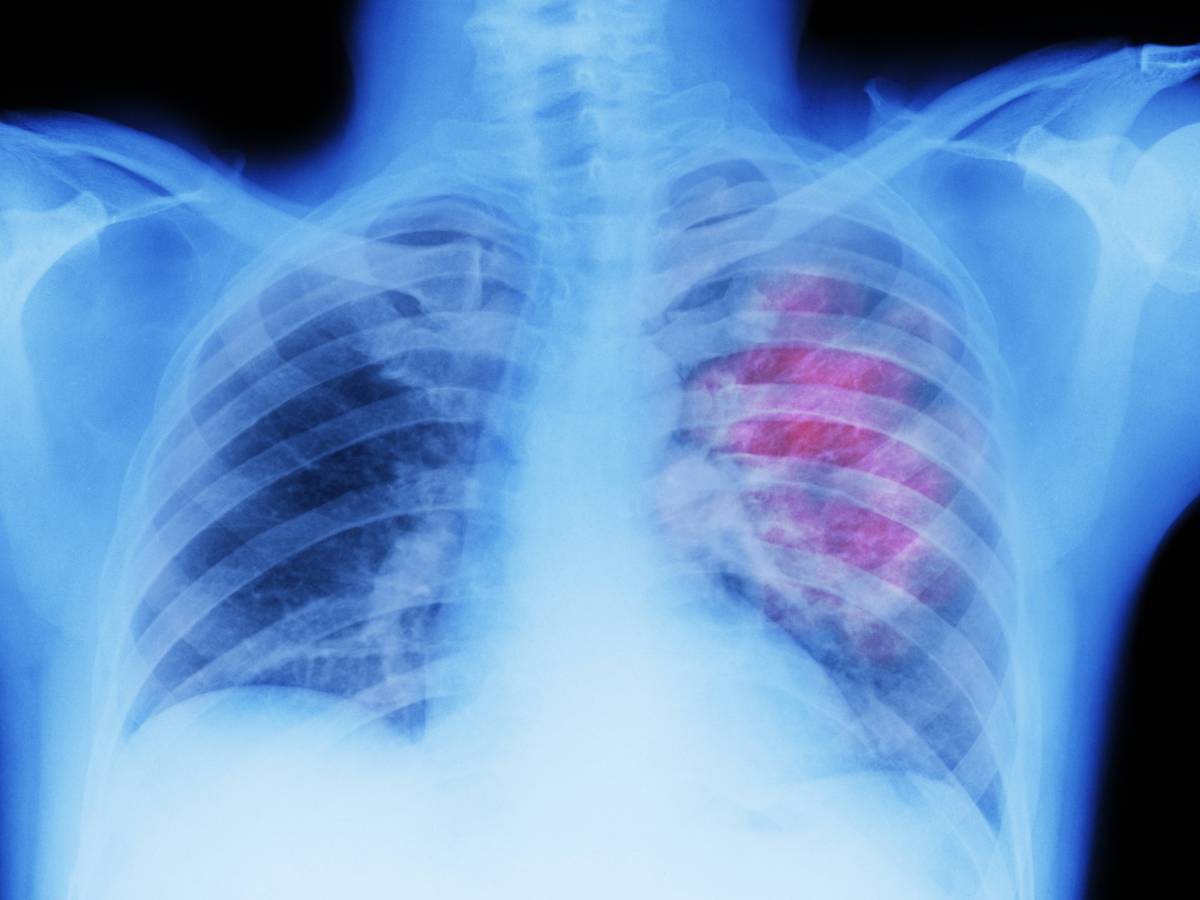

Диагностика

Для того чтобы верно определить причину скопления жидкости и назначить лечение, врачу необходимо провести диагностику. Обследование больного проходит в несколько этапов. Сначала изучают оба легких пациента путем:

- визуализации грудной клетки — при некоторых формах болезни меняется и форма грудины;

- определения болевых точек;

- ультразвукового исследования;

- лабораторного исследования выпота.